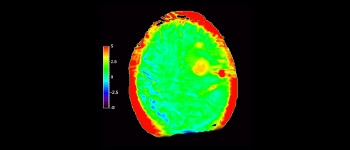

3D T1w TFE 3D APT

Glioblastoma

Cerebro con glioblastoma

con 3D APT